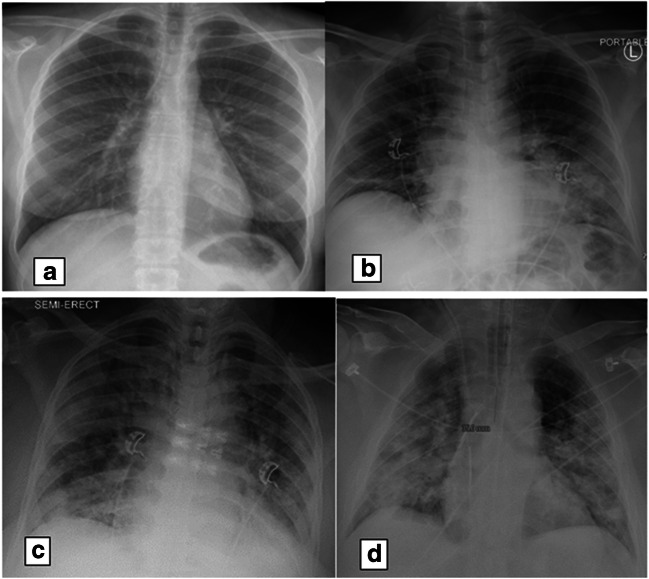

IRB approval was obtained to allow a retrospective review of adult patients (age 21 or older) who presented to the ED with a complaint of fever, cough, dyspnea, or hypoxia and had an initial chest radiograph between 12 March 2020 and 26 March 2020. Waiver of informed consent was approved by the institution. Data was stored on Box (Box, Inc., Redwood City, CA, USA), which is a HIPAA-compliant cloud storage system. Initial data set was extracted with M*Modal Catalyst (M*Modal, Pittsburgh, PA, USA), an advanced query software, of ED chest radiographs with clinical indication of “fever,” “cough,” “dyspnea,” and “hypoxia.” These key words were chosen to widely capture patients with suspected COVID-19 symptoms during the initial pandemic when there was shortage of laboratory testing. One thousand two hundred fifty-six patients satisfied these criteria and a random sample of 416 was taken to be analyzed. The patients’ medical records were reviewed and age, gender and initial oxygen saturation were documented. Also, note was made of history of diabetes and hypertension. If performed, the patient’s SARS-CoV-2 status was recorded along with patient outcome (discharged from ED, admission, or death). The chest radiographs were reviewed by an experienced thoracic radiologist with over 20 years of experience and graded on a scale of 0–3 with grade 0 representing no alveolar opacities, grade 1: < 1/3 alveolar opacities, grade 2: 1/3 to 2/3 alveolar opacities, and grade 3: > 2/3 alveolar opacities (Fig. 1).

Fig. 1.

Visual representation of the grading system for the chest radiographs, in which a grade 0 assigned for normal, b grade 1 assigned for alveolar opacities < 1/3 of lung, c grade 2 assigned for alveolar opacities 1/3 to 2/3 of lung, and d grade 3 assigned for alveolar opacities > 2/3 of lung